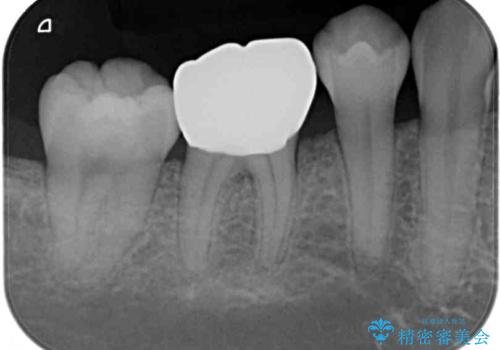

- 奥歯が食事中に歯が欠けて、しみて痛いとのことで来院された患者様です。

レントゲン写真からも、舌側に大きな虫歯があることが分かりました。

症状から神経を取り除く可能性も考慮し、オールセラミッククラウンにて補綴治療することとしました。

速やかに処置を進めたことで症状は落ち着き、治療後しばらくの状態では神経を取り除く可能性は低くなりました。